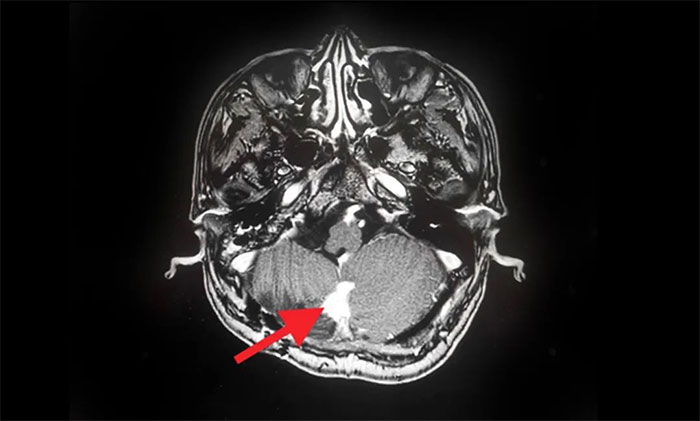

2019年,出现头痛等症状后再次就医。查头颅MRI提示:多发性脑肿瘤,考虑小脑血管母细胞瘤术后复发,基因检测提示VHL(Von Hippel-Lindau,希佩尔- 林道综合征),后采取保守治疗。

▲ MRI影像提示多发脑肿瘤

在伽玛刀治疗后,汪先生身体状况良好,未出现明显并发症,经综合评估顺利出院。8月份,他遵照医嘱来院复查,MRI可见病灶较治疗前明显缩小。